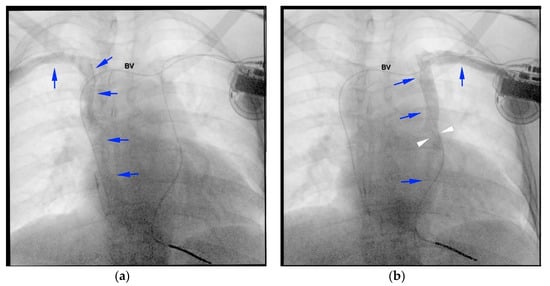

2. Case Report